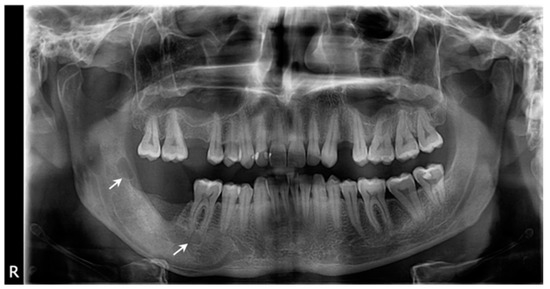

2. Case Presentation